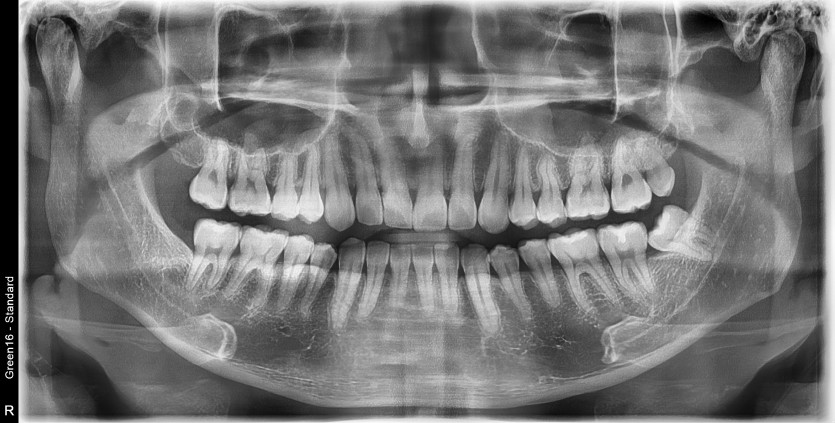

#28,38 사랑니 발치

구강 외과 전문의가 당일 발치했습니다.